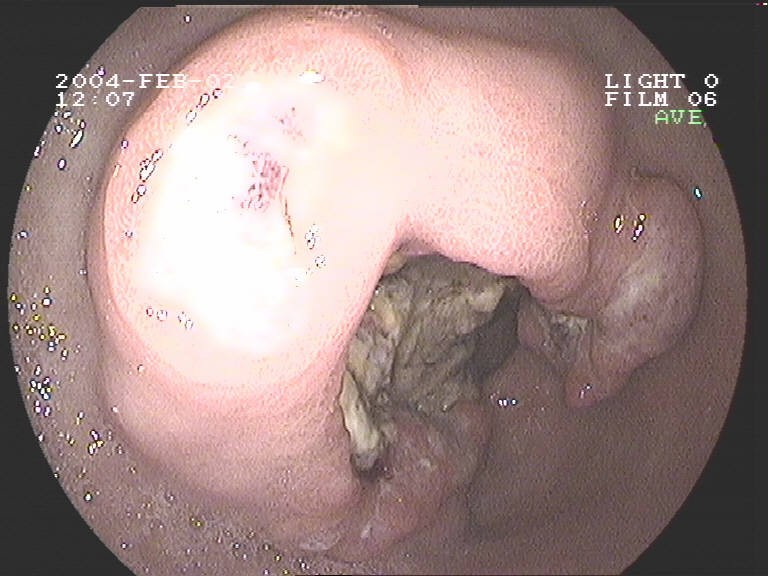

Coloskopie - Dickdarmkarzinom mit deutlicher Stenose (Verengung des Darminnendurchmessers)